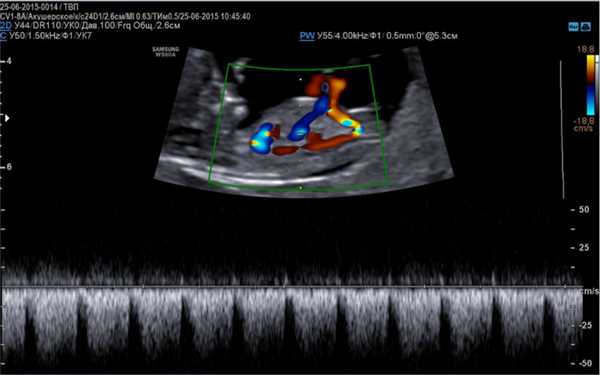

В зависимости от применяемых режимов одновременно выделяют: дуплексное и триплексное УЗГД. Как правило, для оценки внутриутробного состояния плода используют дуплексную допплерографию. При нем обычное серошкальное УЗИ сочетается с одним из режимов допплерографии, который в режиме реального времени передает изображение.

При триплексном сканировании режим УЗИ объединяется с режимом допплерографии и с цветным картированием кровотока, что позволяет оценить анатомию сосуда и его проходимость.

- Цветное картирование - состояние даже мельчайших сосудов и их проходимость кодируется цветом.

- Цветная допплерография. Изображение текущей крови представлено красным или синим цветом в зависимости от направления кровотока и его скорости.